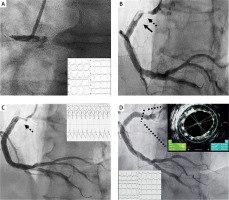

A 64-year-old man with hypertension and type II diabetes presented with an inferior ST-elevation myocardial infarction (STEMI) (Figure 1 A, baseline 12 leads electrocardiogram (ECG)) within 2 h of symptom onset. He was loaded with aspirin and ticagrelor, and 8000 units of unfractionated heparin were administered intravenously (iv). Urgent coronary angiography performed via the right radial artery showed an ostial acute thrombotic occlusion of the infarct-related coronary artery (RCA) (Figure 1 A) with Thrombolysis in Myocardial Infarction (TIMI) grade 0 flow in a left non-dominant unobstructed coronary artery system. After achieving flow with a workhorse guidewire crossing, a severe proximal RCA stenosis with a large thrombus burden (LTB) was revealed (Figure 1 B). To prevent microvascular distal embolization (DE) and the no-reflow (NR) phenomenon [1], up-front iv GpIIb/IIIa tirofiban 25 µg/kg bolus and guide catheter directed intracoronary thrombolysis (ICT) with 10 mg of alteplase were administered without any prior thrombus modification technique such as manual aspiration thrombectomy (MAT) or ballooning. We felt that in the absence of coronary-specific power aspiration catheters, conventional MAT would be ineffective in such an LTB vessel and would probably provoke thrombus migration and embolization. Half an hour after ICT, electrocardiography showed an accelerated idioventricular rhythm, which was well tolerated (Figure 1 C, Cath Lab hemodynamic monitoring system), and angiography demonstrated successful reperfusion with complete thrombus resolution (Figure 1 C). Predilation of the proximal RCA stenosis with a semi-compliant balloon (3.0 × 15 mm) was followed by intravascular ultrasound-guided implantation of a Resolute Onyx 5.0 × 18 mm drug-eluting stent. An excellent angiographical result was obtained following post-dilation with a non-compliant 6.0 × 8 mm balloon (Figure 1 D), with a non-Q MI evolution (Figure 1 D, post-procedure ECG).

A – Baseline 12-lead electrocardiogram (ECG) showing inferior ST-elevation in leads II, III, aVF with the presence of left bundle branch block and an urgent coronary angiography an acute right coronary artery (RCA) occlusion with Thrombolysis in Myocardial Infarction (TIMI) grade 0 flow. B – Workhorse guidewire crossed the obstruction easily and positioned distally in the posterior descending artery (PDA). Severe stenosis (dotted line with arrow) with large thrombus burden (LTB) (black arrow) was revealed proximally in RCA. C – 30 min after intracoronary thrombolysis there was electrocardiographic (typical accelerated idioventricular rhythm, well tolerated) and angiographic evidence of successful reperfusion with TIMI 3 flow in PDA with complete thrombus resolution, and evidence of severe proximal RCA stenosis (dotted line with arrow). D – An excellent angiographical result was obtained following implantation of a Resolute Onyx 5.0 × 18 mm drug-eluting stent post-dilated with a non-compliant 6.0 × 8 mm balloon, based on cross-sectional intravascular ultrasound imaging with the Eagle Eye Platinum ST catheter (Volcano). Post-PCI 12-lead ECG showing inferior non-Q myocardial infarction evolution